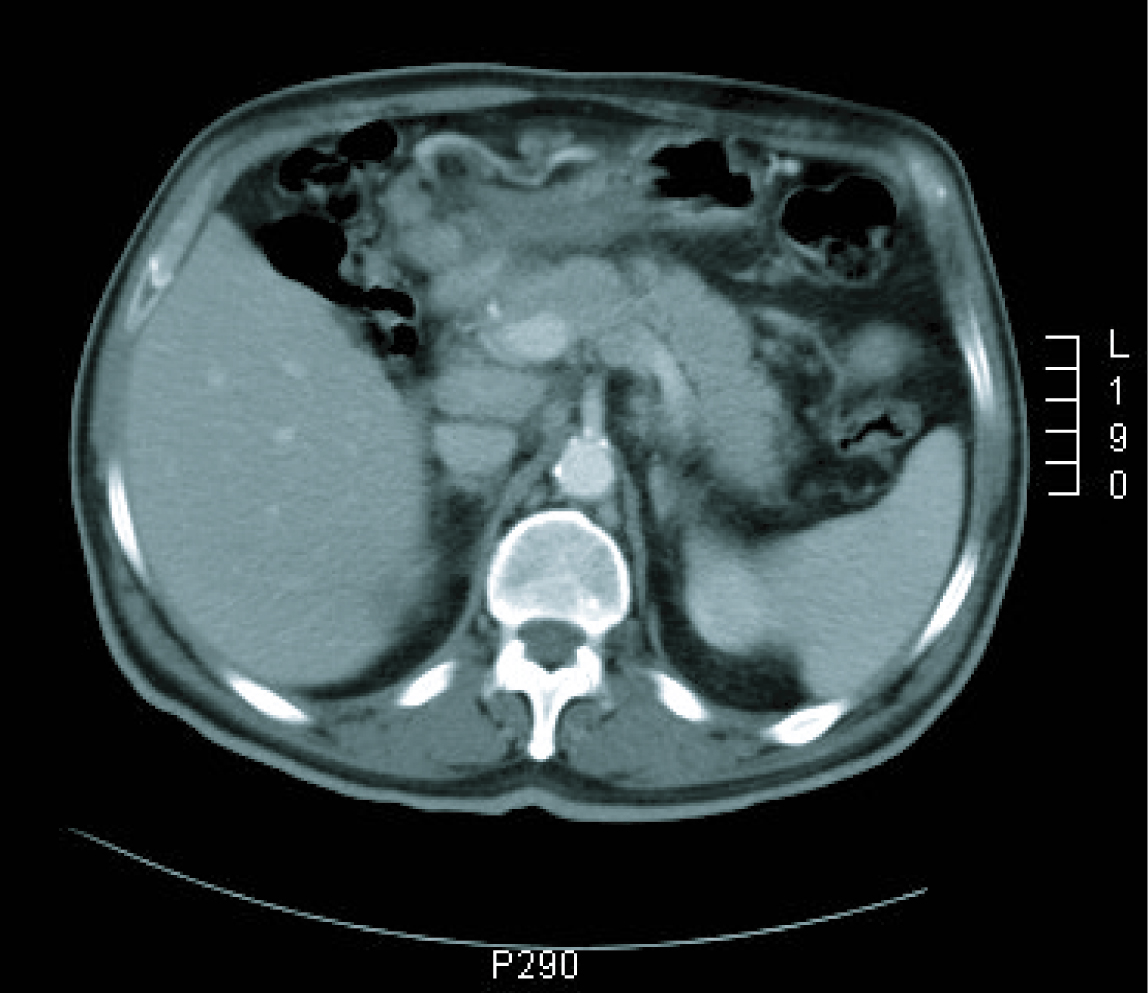

Gastroscopy revealed a 4 cm ulcer in the gastric antrum of uncertain malignancy and a 5 mm ulcer in the body of benign appearance. Anatomical pathology analysis confirmed a diagnosis of intestinal-type gastric adenocarcinoma. It was requested an extended study with CT imaging in order to analyse gastric wall and omental thickening and a number of lymphadenopathies in the gastric, abdominal and retroperitoneal regions (Fig. 1, 2). Analysis showed that tumour markers (CEA and CA 19.9 levels) were not elevated. Given a significant lymphatic component, it was decided to perform an ultrasound-guided fine-needle aspiration (FNA) of the adenopathy, which confirmed a metastatic origin of the adenocarcinoma. Evaluated as an oncology outpatient, the subject presented a maintained general state (with an ECOG 1 performance status), with examination showing a palpable mesogastric mass.

![]() Click for large image | Figure 1. CT imaging at diagnosis. |

![]() Click for large image | Figure 2. CT imaging at diagnosis. |